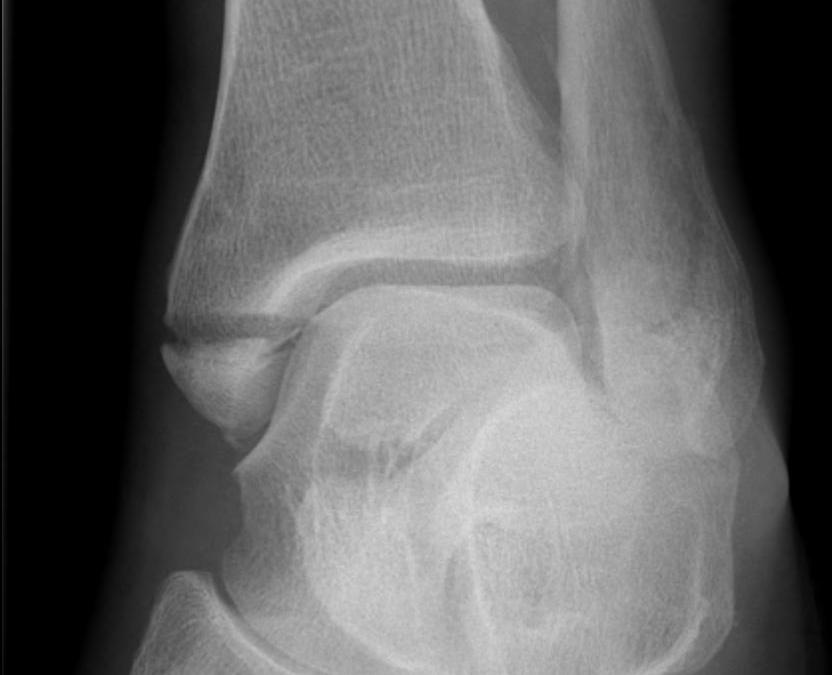

X-ray assessment

3 standard views

AP / Lateral / Mortise

Mortise

- AP with foot internally rotated

- should be symmetrical space around talus

| Increased tibio-fibular clear space | Overlap | Increased medial clear space |

Medial border of the fibula Lateral border of the posterior tibia (incisura fibularis) Measured 1 cm above the plafond |

Overlap of the fibula and the anterior tibial tubercle

Medial talus to lateral medial malleolus |

| <5mm AP and mortise |

> 6 mm AP view > 1 mm mortise view |

< 4mm Equal to superior clear space |

| Syndesmotic injury | Syndesmotic injury |

Deltoid ligament injury Lateral talar shift |

Lateral talar shift / increased medial clear space / deltoid ligament injury

Tibia / fibular overlap < 1mm / syndesmotic injury